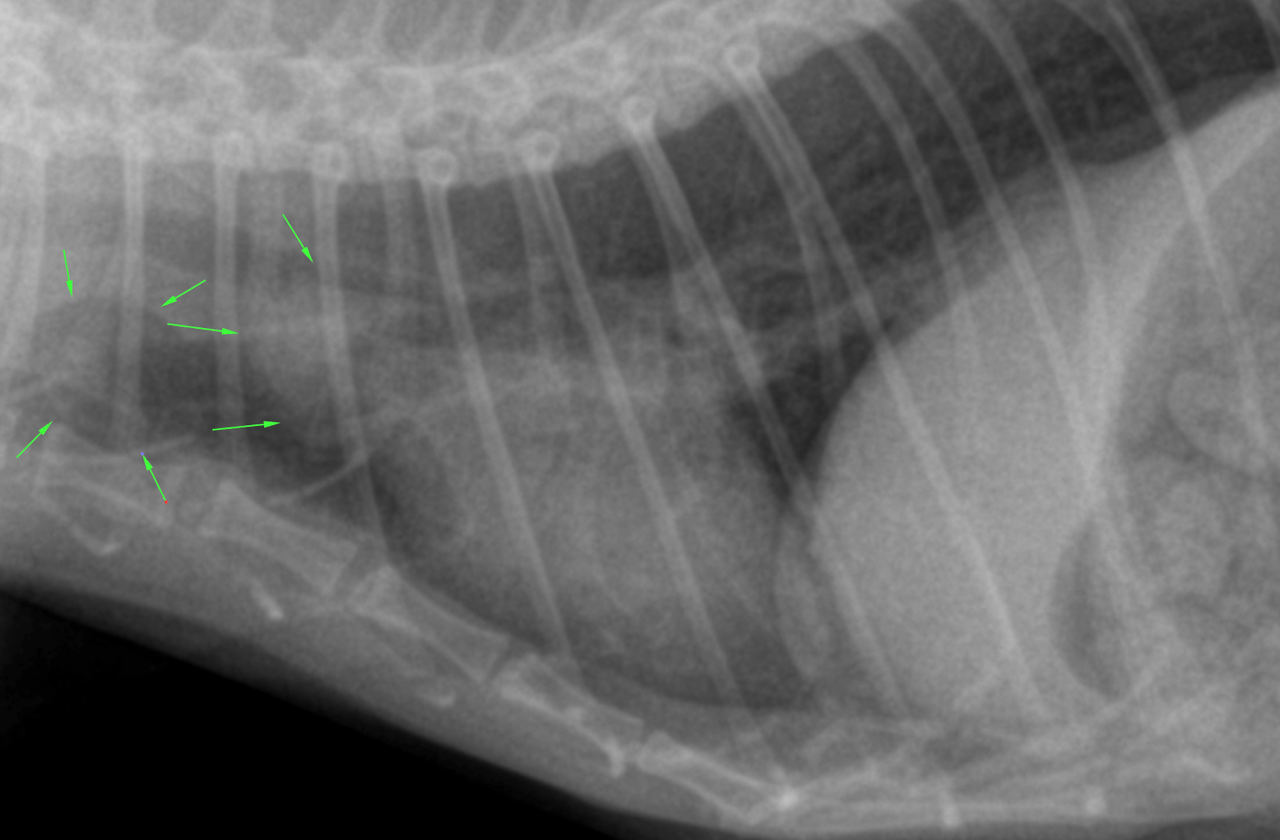

lateral and DV thorax, right lateral neck – The patient was thin.

Osseous structures:

Mild degenerative changes were associated with the axial skeleton.

Intrathoracic structures:

The esophagus was not seen. The course of the trachea was normal. The cardiac silhouette was within normal limits. There was a redundant aortic arch. The caudal vena cava and pulmonary vessels were thin. There was no mediastinal widening.

The chest was funnel shaped. The lung presented a mild generalized thinwalled bronchointerstitial pattern. There was no air trapping. There were no signs of expiratory obstruction. There were no signs of pneumonia, congestive heart failure, pulmonary edema or pleural effusion.

DX

The lung changes are most compatible with a normal age related bronchointerstitial pattern.

The were no radiographic signs of cardiac disease or congestive heart failure.

Signs specific for chronic airway obstruction are lacking rendering feline asthma very unlikely. The aerophagia may be a function of a primary intestinal disease, a metabolic disorder, pain or stress. Rule out metabolic & spinal disease and enforce abdominal ultrasound for further diagnostic workup.